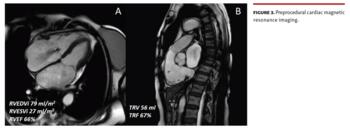

The efficacy of transcatheter edge-to-edge tricuspid valve repair (TTVR) has been recently demonstrated not only for the reduction of tricuspid regurgitation (TR) but also in terms of right ventricular remodeling. We report the case of a 78-year-old female patient with a history of atrial fibrillation and severe isolated TR in New York Heart Association functional classification III despite optimal medical therapy. The preprocedural transesophageal echocardiography (TEE) showed severe TR associated with Ebstein’s-like valve displacement, and dilation of the right atrium and ventricle with “atrialized” portion. The tricuspid annulus plane systolic excursion was preserved (20 mm) with acceptable systolic pulmonary artery pressure (PAP) of 30 mmHg (Figure 1 and Figure 2; Video Series).